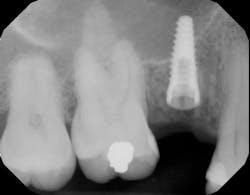

Appropriate alignment of the x-ray beam is a critical factor in obtaining clear and accurate radiographic images, reducing distortion, and improving diagnostic quality during dental implant osteotomy preparation. When diagnostic radiographic data transfer is accurate, the dental implant has a higher probability of being placed appropriately (figures 6 and 6a).